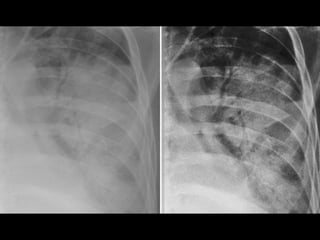

Asbestosis

• #47 Asbestosis

• #48 Asbestosis